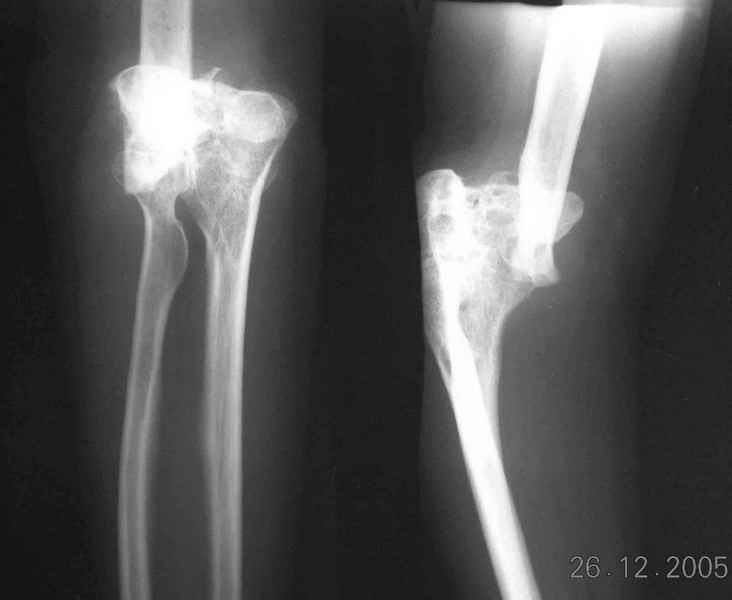

The recent x rays show established Non union with poor quality bone in the distal fragement. The joint is also appearing degenerate. In view of the multiple failed reconstructive surgeries, an Elbow replacement would seem reasonable.

However it would have to be a fully constrained one as there would be missing bone stock.

Obviously there is no elbow joint...the options are few: (from the worst to the "best"...if any)

3. Total elbow replacement (semi constrained - as no ligaments to stabilize the joint) - Coonrad-Morrey, Discovery - Biomet - considering his age there is limited indication for that procedure.

4. There is limited experience with total elbow allograft replacement with some rate of successes on one hand and high rate of complications on the

other hand. I personally would try this option as it is a reversible procedure and one could in a case of failure to replace it with prosthesis